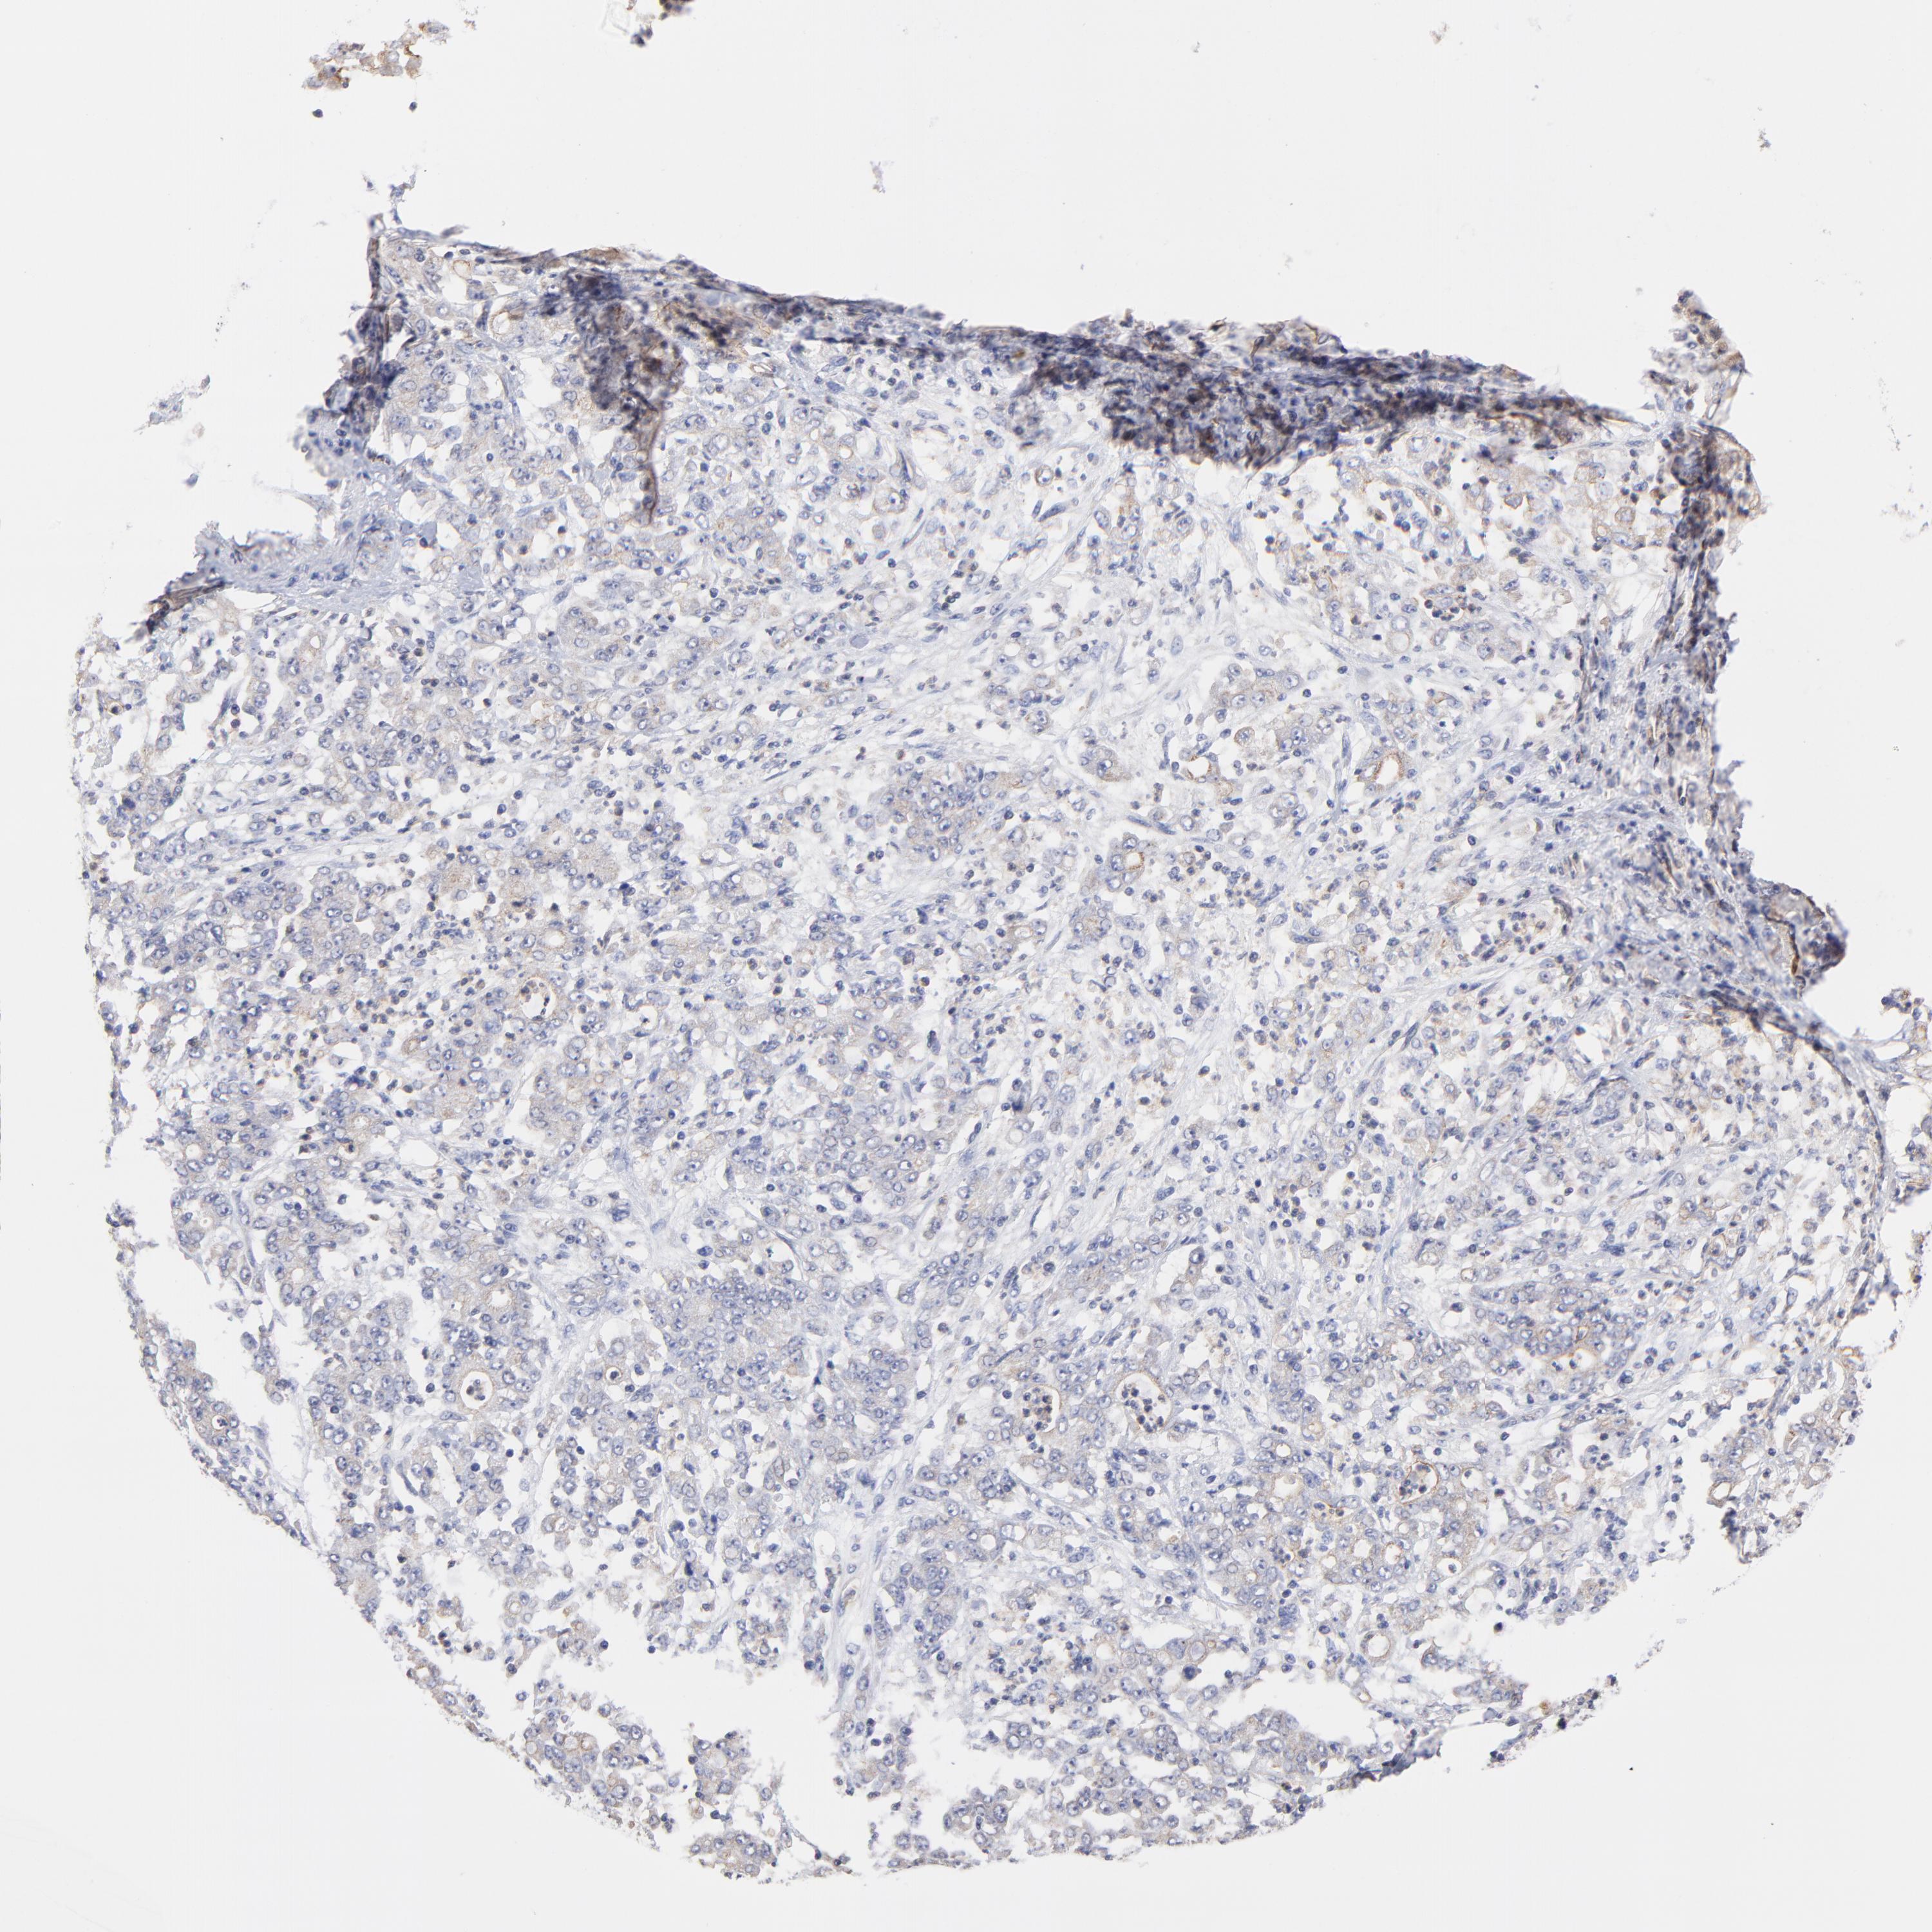

STOMACH CANCER - Protein expressioni

A mouse-over function shows sample information and annotation data. Click on an image to view it in a full screen mode. Samples can be filtered based on level of antibody staining by selecting one or several of the following categories: high, medium, low and not detected. The assay and annotation is described here.

Note that samples used for immunohistochemistry by the Human Protein Atlas do not correspond to samples in the TCGA dataset.

Antibody stainingi

Antibody staining in the annotated cell types in the current human tissue is reported as not detected, low, medium, or high, based on conventional immunohistochemistry profiling in selected tissues. This score is based on the combination of the staining intensity and fraction of stained cells.

Each image is clickable and will lead to virtual microscopy that enables deeper exploration of all samples and also displays staining intensity scores, fraction scores and subcellular localization as well as patient and tissue information for each sample.

Antibody HPA003239

Staining

High

Medium

Low

Not detected

Intensity

Strong

Moderate

Weak

Negative

Quantity

>75%

75%-25%

<25%

None

Location

Nuclear

Cytoplasmic/membranous

Cytoplasmic/membranous,nuclear

Adenocarcinoma, NOS

Adenocarcinoma, High grade